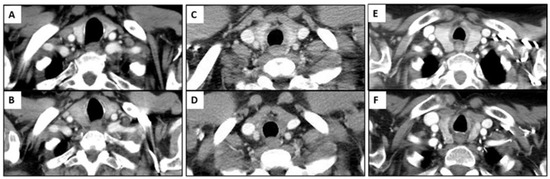

3.2. Immune-Related Thyroiditis Based on Imaging Findings

3.5. Temporal Changes in the CT Findings Correlating with TSH